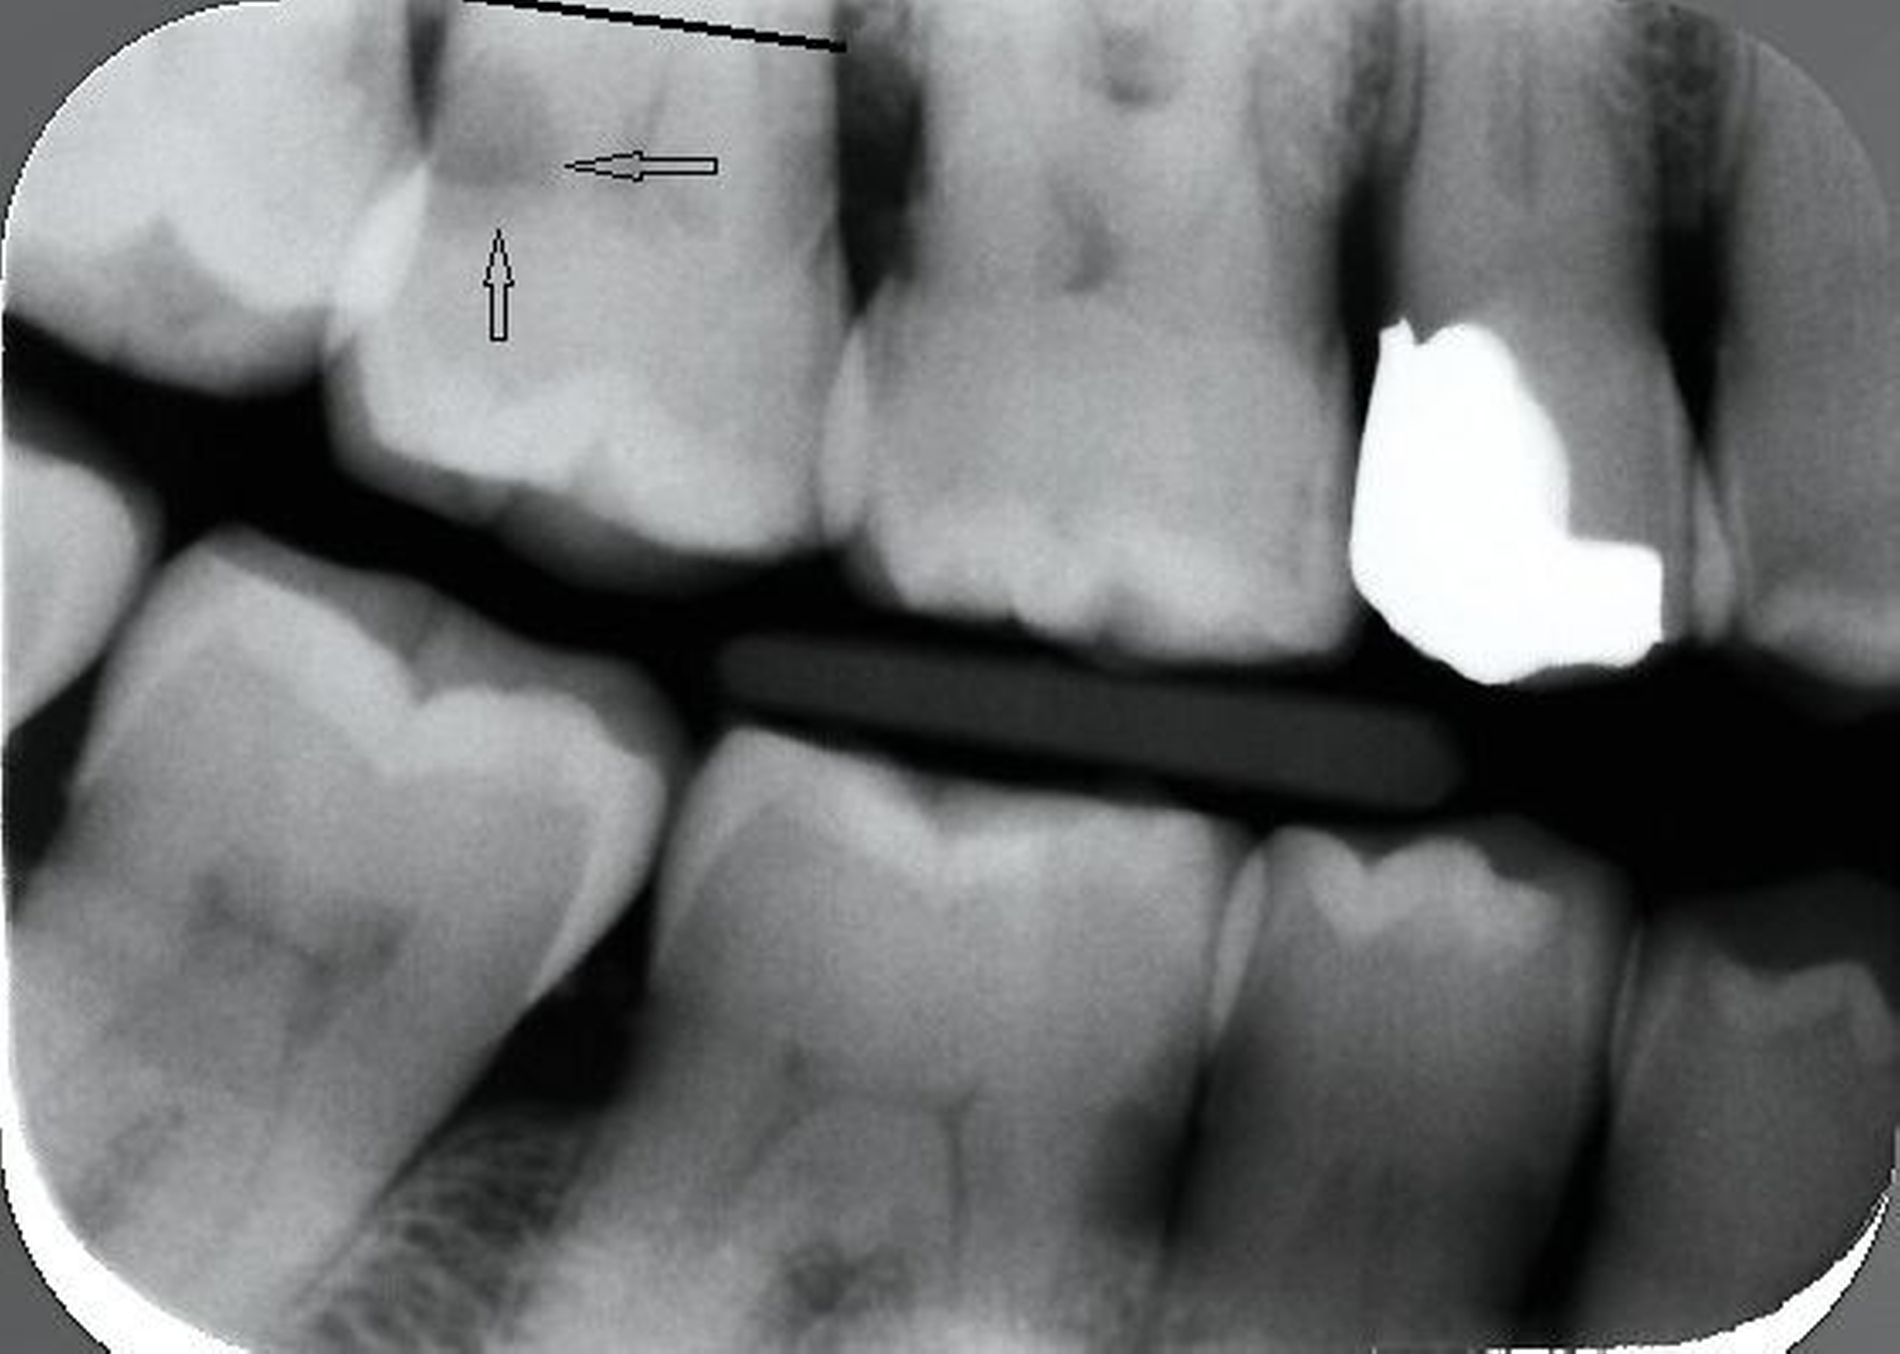

Sollten die interdentalen Bereiche der Wurzeloberfläche nicht einsehbar sein, sind Bissflügelaufnahmen hilfreich. Allerdings müssen kariöse Läsionen von Artefakten, sogenannten „Burn-out-Effekten“, unterschieden werden. Darunter versteht man eine Aufhellung im Zahnhalsbereich, die durch die relativ geringere Abschwächung von Röntgenstrahlung im Bereich des nur durch Gingiva bedeckten Zahnareals und durch die interdental geringere Masse des Zahnes entstehen kann. Da die Voraussetzung für die Entstehung von Wurzelkaries eine freiliegende Wurzeloberfläche ist, bilden Aufhellungen im Röntgenbild, die mit Rezessionen des Knochens vergesellschaftet sind, ein relativ sicheres Kriterium für Wurzelkaries (Abbildung 5). Die Röntgendiagnose sollte klinisch durch Sondierung der relevanten Areale verifiziert werden.